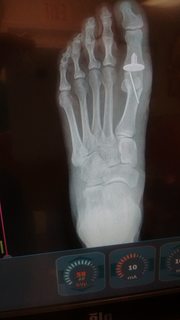

Hey Guys, I had a small surgery on my left big toe a couple of weeks ago. I was there initially to have some bone spurs removed. The doc told me that he might have to do a partial joint replacement, depending on what he found. Turns out the joint was so deteriorated, that he did have to do the joint replacement. The flat piece with the piece under it is called a HEMI. So, now, as an old Mopar man, I can honestly tell people that I have a hemi! LOL I'm just waiting for it to be fully healed so I can see how much faster I can run. Here it is. Just thought I'd add a little humor to everyones Sunday.

I think they put a plastic body push pin in there, derf. Ripped off the insurance company! LOL Hammer toes, derf. Must have inherited from my mother as she had it really bad. Either that or from wearing all the hand me down shoes from my older brothers when I was a kid. Disadvantage of being the youngest of 5 boys.